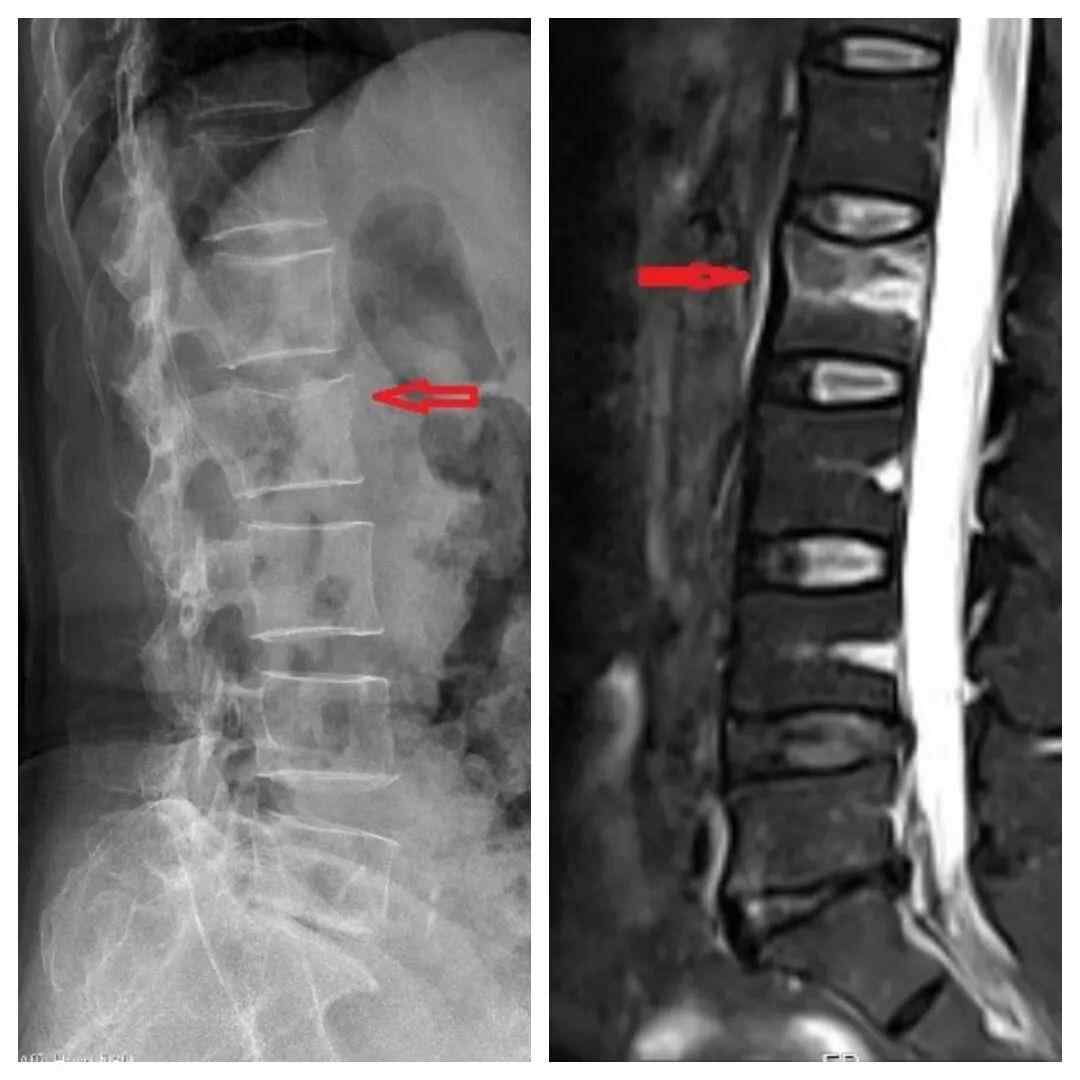

丁阿姨的X片(左)、磁共振(右),提示腰2椎体骨折